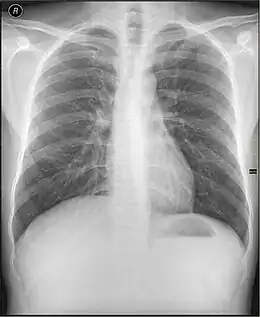

Les informations provenant des différentes structures traversées par le faisceau de rayonnements sont projetées sur un même plan pour former l'image. Par conséquent, il est souvent nécessaire de réaliser deux projections, à différentes incidences, pour pouvoir localiser une structure dans les trois dimensions de l'espace. Par exemple, en médecine, il s'agit fréquemment d'incidences de face et de profil. La loi d'atténuation des photons explique l'atténuation différentielle du faisceau à travers différentes structures, ce qui est à l'origine du contraste radiographique.

L'objet à radiographier, placé entre les positions et , à distance de la source pour que l'on puisse considérer qu'il est soumis à faisceau homogène de photons X ou gamma. Au fur et à mesure que le faisceau de photons traverse l'objet, il est atténué en fonction de l'épaisseur traversée et du coefficient d'atténuation . Ce coefficient d'atténuation dépend de l'énergie du photon et du numéro atomique Z de la structure rencontrée à la profondeur . L'organisme humain possède des tissus comme les os, très opaques aux photons, possédant donc un coefficient d'atténuation très élevé. Cela vient du fait que le tissu osseux est composé d'éléments de numéro atomique élevé comme le calcium. Le corps est aussi composé de tissus mous, peu opaques aux rayons X. Parmi eux, on différencie les organes de densité hydrique car composés essentiellement d'eau (muscles, foie) des densités graisseuses dont le coefficient d'atténuation est légèrement plus faible. Enfin, le poumon étant essentiellement composé d'air, il est qualifié d'organe de densité aérique. En effet le tissu pulmonaire, comme l'air, laisse passer la quasi-totalité des rayonnements. À la sortie du patient, le faisceau de photons n'est plus homogène mais est caractéristique des tissus traversés, on parle d'image radiante . Ces photons interagissent avec le détecteur, y déposant une énergie représentative des tissus traversés. Selon le mode de fonctionnement du détecteur, cette énergie sera utilisée pour produire l'image. La forte différence de coefficient d'atténuation entre les os et les autres tissus, crée un fort contraste de l'image, ce qui fait des rayons X un excellent outil d'imagerie osseuse. Pour obtenir une image d'organes n'ayant pas une densité spécifique, il est possible d'apporter in situ un produit de contraste de forte densité. C'est le cas pour l'imagerie des vaisseaux (injection intraveineuse d'iode), pour l'imagerie du système digestif (ingestion ou injection de baryte, à base de baryum), pour l'imagerie des articulations, ou arthroscopie (injection intra-articulaire d'iode) ou encore par exemple pour l'imagerie du système de reproduction de la femme, ou hystéroscopie (injection d'iode).